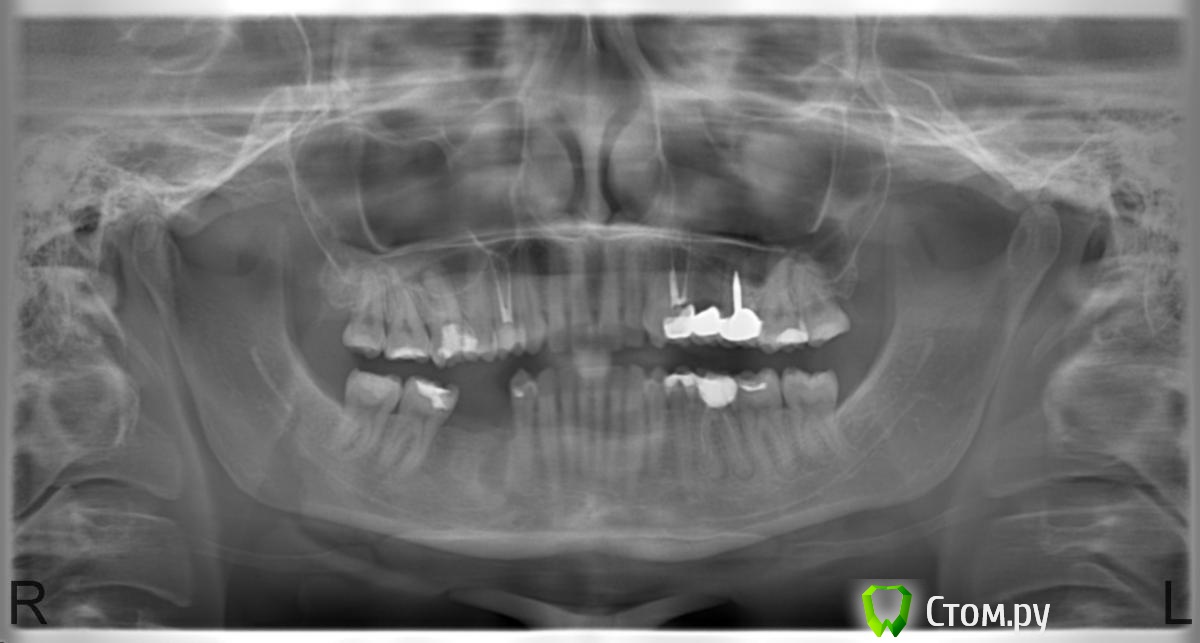

Krasnodarka Опубликовано 29 августа, 2014 Поделиться Опубликовано 29 августа, 2014 Добрый день, уважаемые стоматологи!Прошу Вас посмотреть снимок и дать рекомендации.Ровно месяц назад поставили мостовидный протез. Со дня постановки вкладки, пока протез готовился, ощущала ноющую боль в шестерке при горячем чае, врач отвечал, что болеть там ничего не может, т.к. зуб уже давно депульпирован(временную коронку мне не ставили на этот зуб).Просила врача установить мост на временный цемент, вроде не реагировал зуб, но после установки на постоянный, зуб реагирует на горячее, иногда на надкусывание. Не сильно, но все же.Посмотрите, все ли там в порядке, качественно ли запломбированы каналы в обточенных зубах.Скоро готовить зубы и ставить мост на нижней челюсти, но есть сомнения в качестве работы терапевта...Буду признательна за помощь. Ссылка на комментарий

Art 7 Опубликовано 29 августа, 2014 Поделиться Опубликовано 29 августа, 2014 Скорее всего пропущен канал. Снимать и переделывать Ссылка на комментарий

Art 7 Опубликовано 29 августа, 2014 Поделиться Опубликовано 29 августа, 2014 Подскажите, мост новый нужно будет делать или на этот же поставят? Вообще надо переделывать полностью, но в шестом зубе у вас стоит вкладка с довольно большой корневой частью и извлечь её будет очень проблематично. В целом ситуация не простая, есть проблема в каналах но доступ к ним замурован. Ссылка на комментарий

Art 7 Опубликовано 29 августа, 2014 Поделиться Опубликовано 29 августа, 2014 ...как действовать в этой ситуации?у 4-го зуба тоже каналы не допломбированы?По этому снимку сложно судить, лучше сделать прицельные снимки, как посоветовал коллега. Как действовать? Думаю попытаться извлечь вкладку надо, но нужно быть готовой к удалению зуба. Ссылка на комментарий

Krasnodarka Опубликовано 2 сентября, 2014 Автор Поделиться Опубликовано 2 сентября, 2014 Вы не поняли. Обращать внимание врача на снимке ни на что не нужно. Нужен грамотный доктор,который обратит внимание на все самостоятельно. В Краснодаре много хороших врачей,некоторые есть на форумеВрачи снова убеждали, что все замечательно, что канал запломбирован резорцин-формалин....чего-то там, который не контрастен на рентгене, в 24 зубе некая прокладка, которая тоже неконтрастна...Может такое быть на самом деле? P.S. Ушла из этой клиники. Ссылка на комментарий